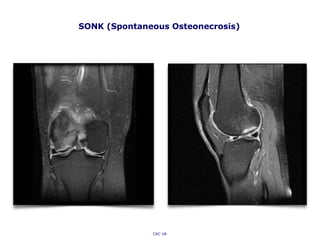

SONK (Spontaneous Osteonecrosis)

CKC UK

• Spontaneous Osteonecrosis (SONK): is the term used to describe a

subchondral insufficiency fracture that causes osteonecrosis. MRI

appearance: a thin linear hypointense subchondral focus on T1W and

T2W that blends in with overlying cortex and is typically surrounded

by diffuse BME. With or without subchondral fractures/deformity.

Spontaneous Osteonecrosis (SONK)

• Ahlback et al first described

spontaneous osteonecrosis of the

knee as a distinct clinical entity

in 1968.

• Osteonecrosis of the knee has

also been described as a

postsurgical complication

following arthroscopic

meniscectomy (Muscolo et al.,

Prues-Latour et al.) and following

radiofrequency-assisted

arthroscopic treatments,

mainly in 50+ age groups.

• The pathophysiology of

osteonecrosis following these

arthroscopic procedures is not

fully understood (vascular

isufficiency, trabecular

microfractures?), or, more

likely, a consequence of pre-

arthrosopy osteopoenia and

altered focal biomechanics

(bone density should be

looked into).